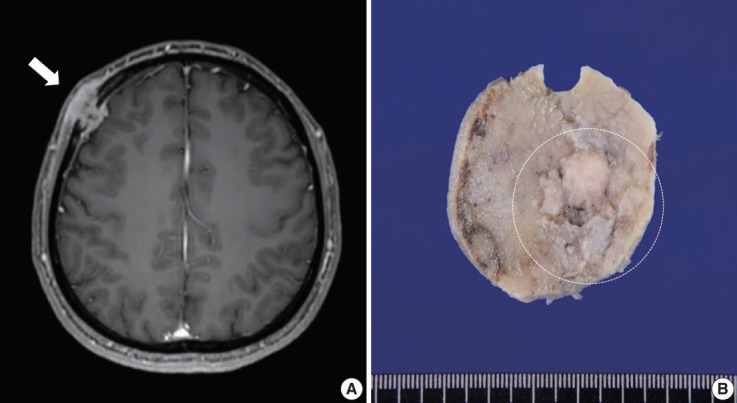

横纹肌肉瘤(RMS)是一组异质性肿瘤,偶尔会在免疫组化(IHC)中表达上皮标记物。我们在此报告了一例颅骨RMS患者,该患者的细胞形态学特征为EWSR1融合、无性淋巴瘤激酶(ALK)和细胞角蛋白表达。一名 40 岁的男子因前额肿块就诊。他接受了手术切除,术中获得了冷冻标本。壁细胞学检查显示散在或聚集的纺锤形和上皮样细胞。IHC 显示,切除的肿瘤细胞中 desmin、MyoD1、细胞角蛋白 AE1/ AE3 和 ALK 阳性。虽然荧光原位杂交发现了EWSR1重排,但没有发现ALK和TFCP2重排。尽管患者接受了辅助化疗,但仍在确诊后10个月死于肿瘤进展。我们强调,RMS 中有一部分可表达细胞角蛋白并表现出特征性的组织形态学,这意味着需要进行特定的分子检查。

Rhabdomyosarcoma (RMS) comprises of heterogeneous group of neoplasms that occasionally express epithelial markers on immunohistochemistry (IHC). We herein report the case of a patient who developed RMS of the skull with EWSR1 fusion and anaplastic lymphoma kinase (ALK) and cytokeratin expression as cytomorphologic features. A 40-year-old man presented with a mass in his forehead. Surgical resection was performed, during which intraoperative frozen specimens were obtained. Squash cytology showed scattered or clustered spindle and epithelioid cells. IHC revealed that the resected tumor cells were positive for desmin, MyoD1, cytokeratin AE1/ AE3, and ALK. Although EWSR1 rearrangement was identified on fluorescence in situ hybridization, ALK, and TFCP2 rearrangement were not noted. Despite providing adjuvant chemoradiation therapy, the patient died of tumor progression 10 months after diagnosis. We emphasize that a subset of RMS can express cytokeratin and show characteristic histomorphology, implying the need for specific molecular examination.